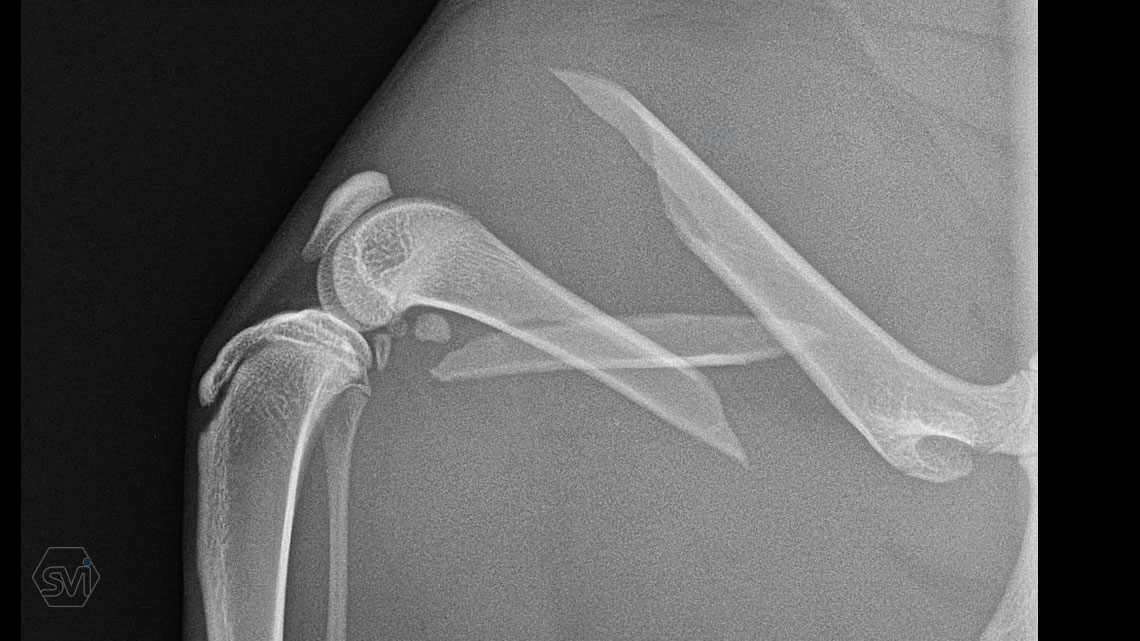

What used to be a nightmare type of surgery is slowly becoming my favorite: the humerus distal Y fracture